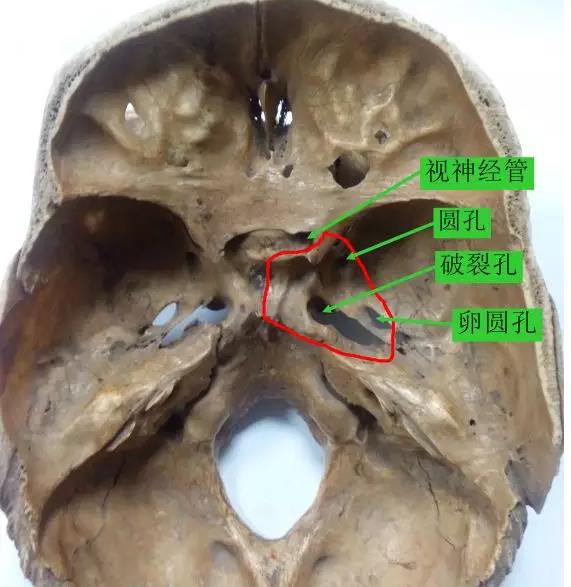

由于腫瘤沿咽旁筋膜擴展至巖蝶區的破裂孔、顳骨巖尖、卵圓孔、圓孔和蝶骨旁的海綿竇,可出現第Ⅱ~Ⅵ對腦神經受累時的表現。臨床上首先受累的多為第Ⅵ對外展神經,然后依次為第Ⅴ3,2,1、Ⅲ、Ⅳ對腦神經。主要表現為瞳孔散大、光反射消失、眼瞼下垂、復視、眼球各方運動受限或固定、三叉神經第1、2支分布區痛覺減退、角膜反射消失等。